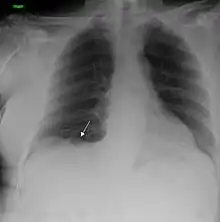

A chest X-ray showing a tumor in the lung (marked by arrow) | |

Performing a chest radiograph is one of the first investigative steps if a person reports symptoms that may be suggestive of lung cancer. This may reveal an obvious mass, the widening of the mediastinum (suggestive of spread to lymph nodes there), atelectasis (lung collapse), consolidation (pneumonia), or pleural effusion.[15] CT imaging of the chest may reveal a spiculated mass which is highly suggestive of lung cancer, and is also used to provide more information about the type and extent of disease. Bronchoscopic or CT-guided biopsy is often used to sample the tumor for histopathology.[13]

Lung cancer often appears as a solitary pulmonary nodule on a chest radiograph. However, the differential diagnosis is wide. Many other diseases can also give this appearance, including metastatic cancer, hamartomas, and infectious granulomas caused by tuberculosis, histoplasmosis or coccidioidomycosis.[65] Lung cancer can also be an incidental finding, as a solitary pulmonary nodule on a chest radiograph or CT scan done for an unrelated reason.[66] The definitive diagnosis of lung cancer is based on the histological examination of the suspicious tissue[2] in the context of the clinical and radiological features.[12]